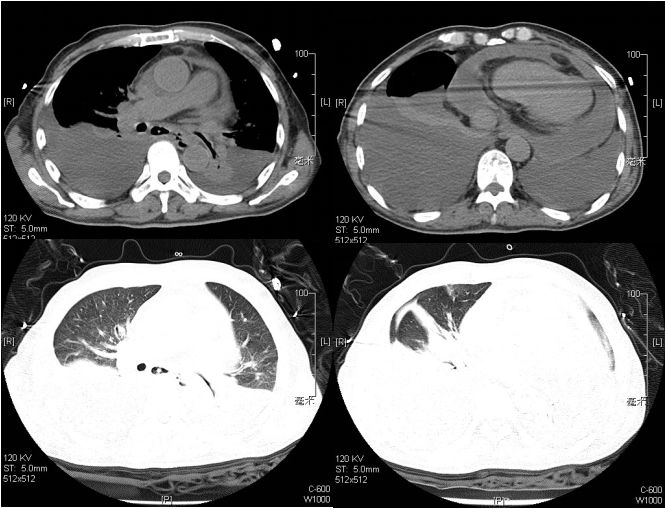

2016年1月28日 胸部CT示病变明显吸收(图8)。

图8. 2016.1.28胸部CT示抗真菌+激素治疗20天病灶明显吸收

遂予以出院,回当地医院继续抗真菌治疗。出院后随访至今,患者病情稳定(图9)

图9.2016.5.5当地医院复查胸部CT示双侧胸水及心包积液明显吸收,纵隔淋巴结明显缩小(抗真菌治疗4月)